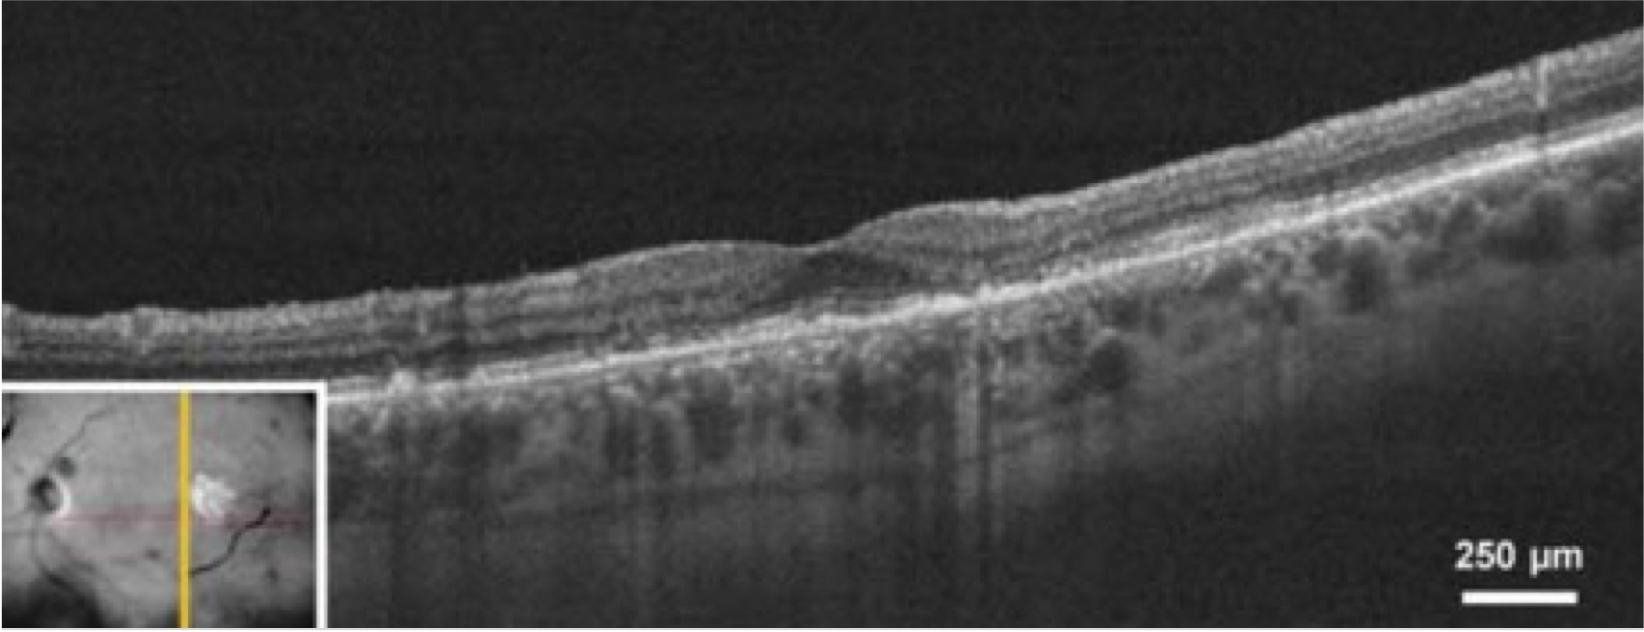

Tomografía de coherencia óptica (TCO)

La TCO es una importante técnica de imagen para el diagnóstico y seguimiento de la DMAE. Toma imágenes transversales de la retina y proporciona una evaluación detallada de la salud de la misma. La TCO puede medir el grosor de la retina, identificar las drusas y la neovascularización coroidea, que son características típicas de la DMAE.8,9